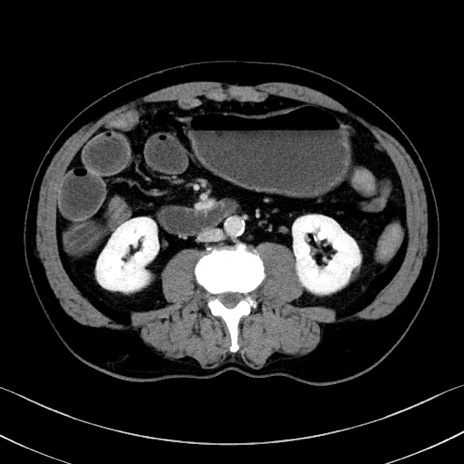

冠状断像

症例35(横断像)

【症例】70歳代 男性

【主訴】腹部膨満、嘔吐

【現病歴】昨日より腹部膨満感出現。本日増悪し、仙痛出現。嘔吐あり、受診。

【既往歴】糖尿病、胆摘後

【身体所見】BP 149/80mmHg、HR 74/min、BT 35.9℃、腹部:膨満、軟、圧痛なし。腸雑音減弱あり。上腹部正中切開瘢痕あり。

【データ】WBC 13500、CRP 1.72